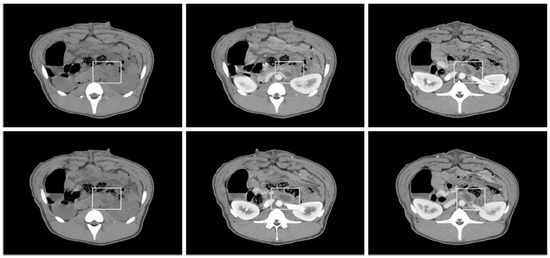

2.5. CT Evaluation

3.3. CT and Necropsy